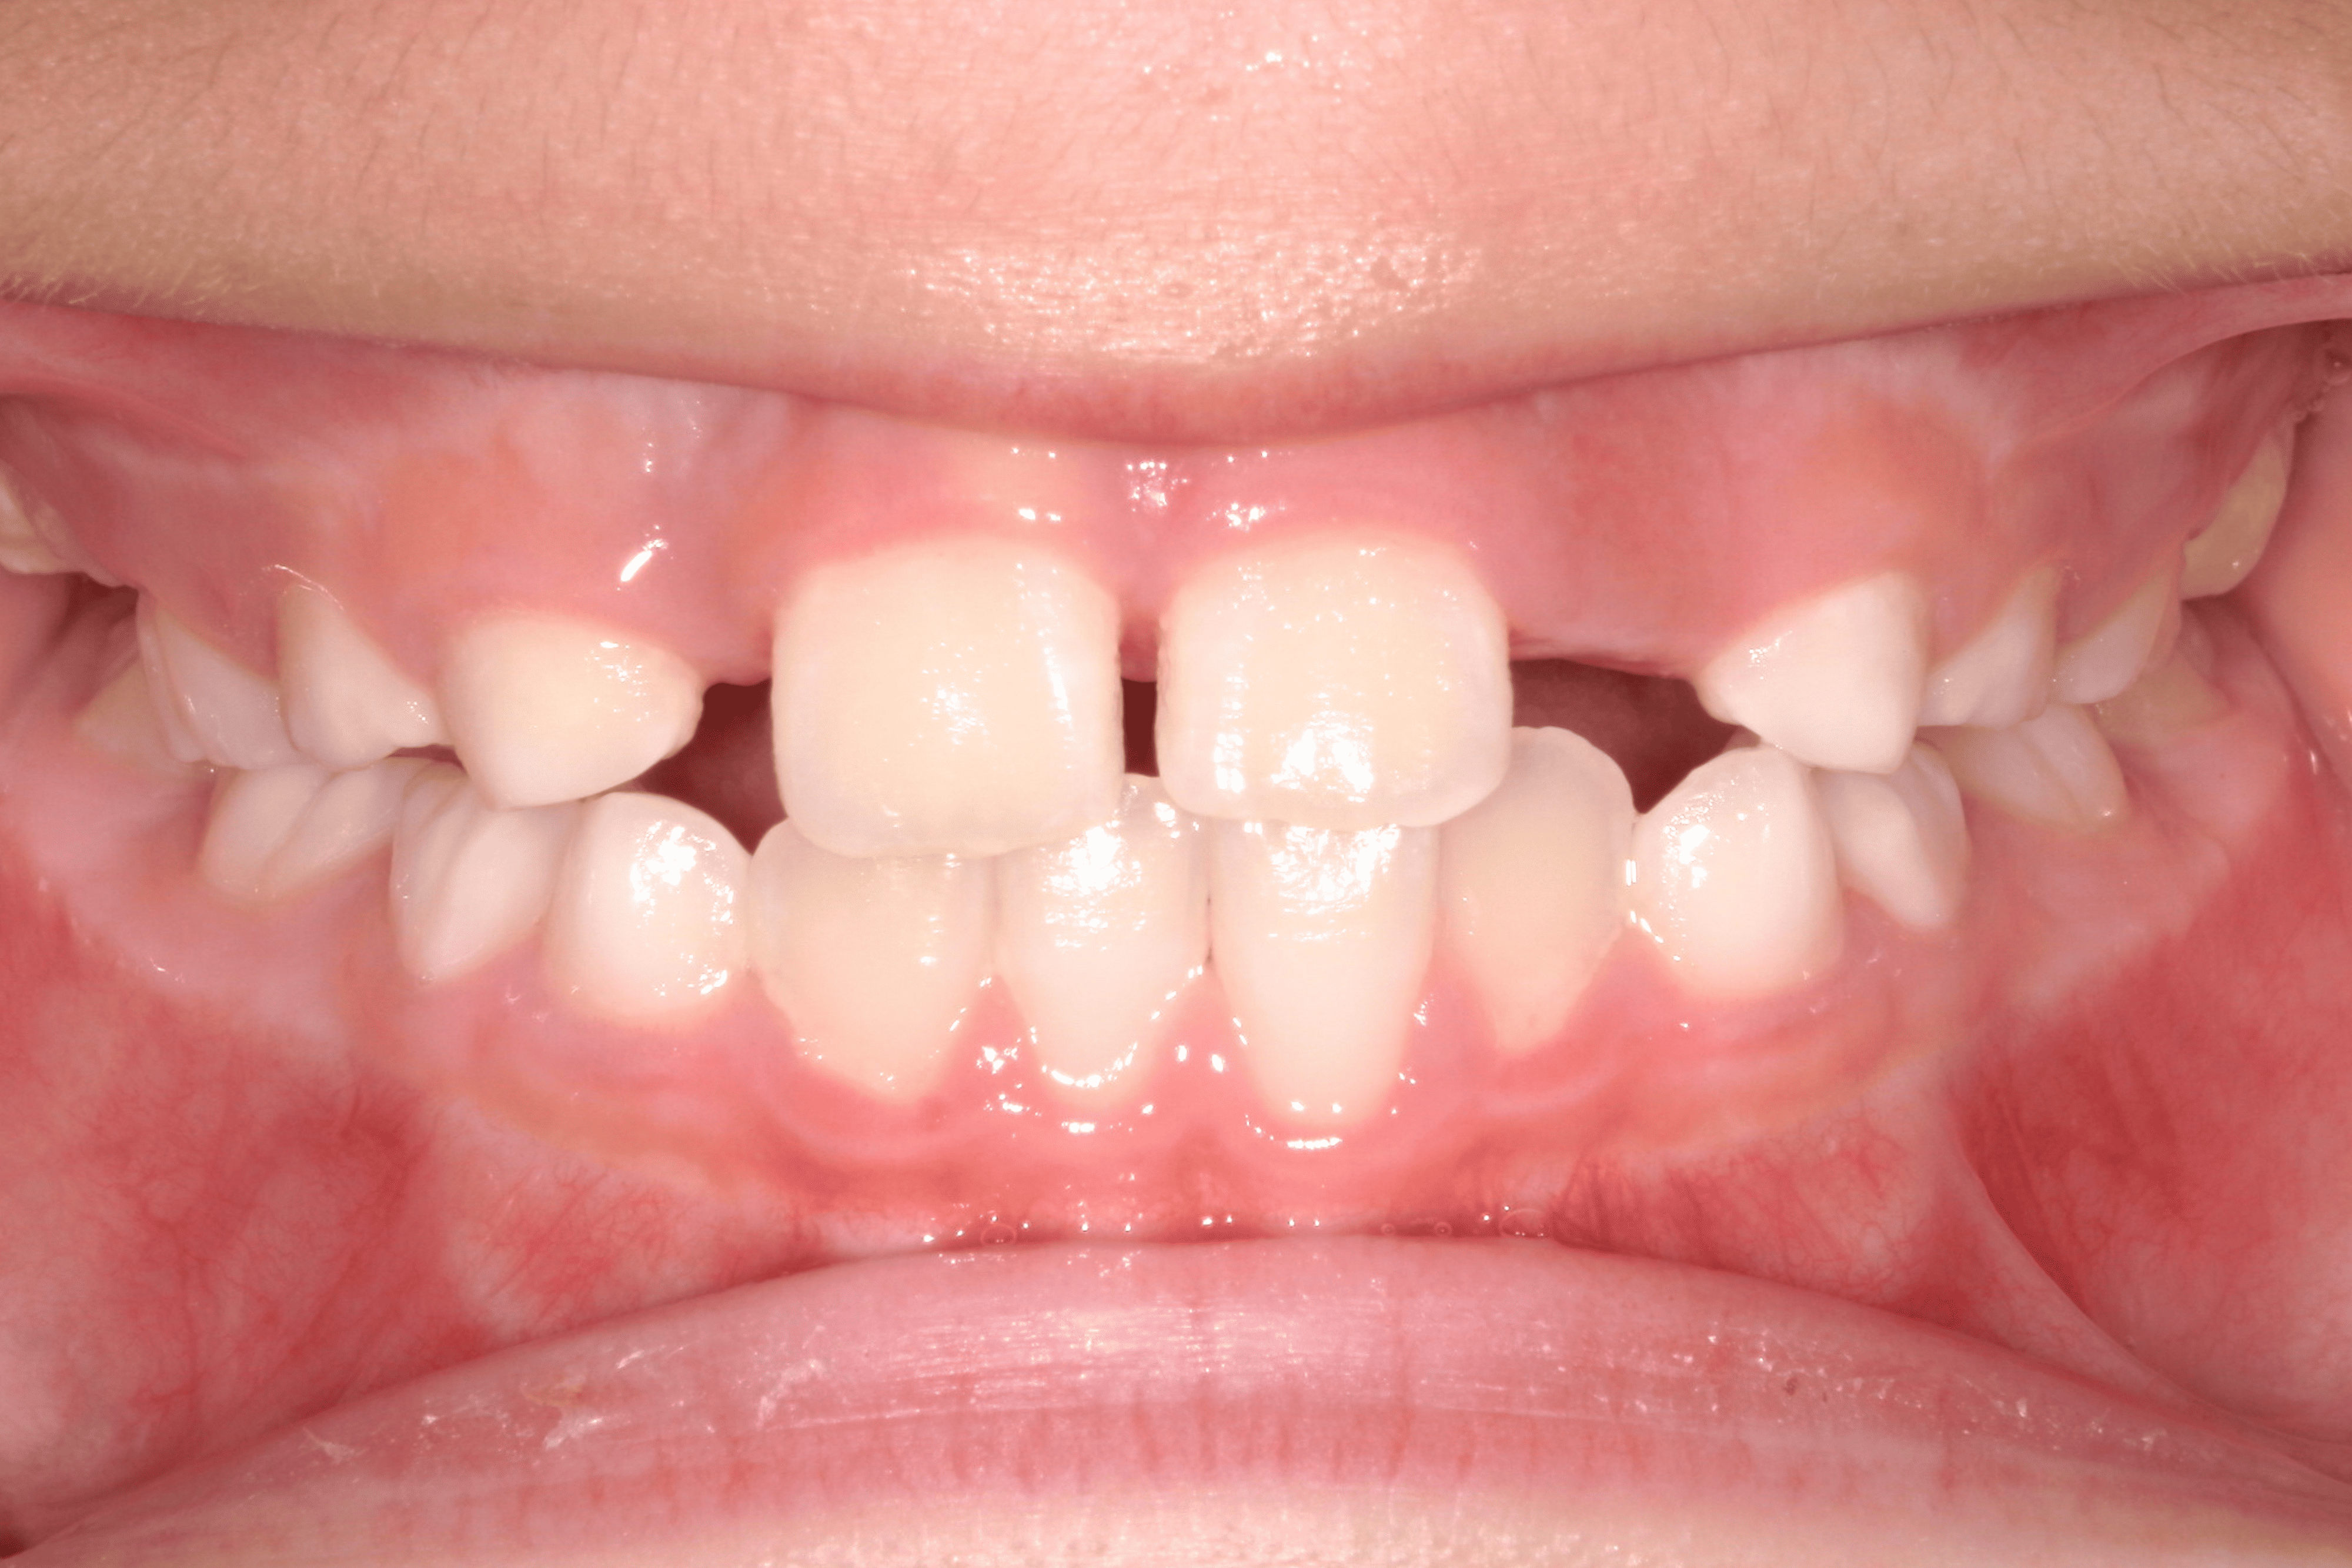

歯並びが気になる男の子の症例

Before

After

| 患者様の主訴 | スペース不足による叢生 |

|---|---|

| 治療内容 | バイオネーター |

| 治療期間 | 1年間 |

| 治療費用 | 330,000円(税込) |